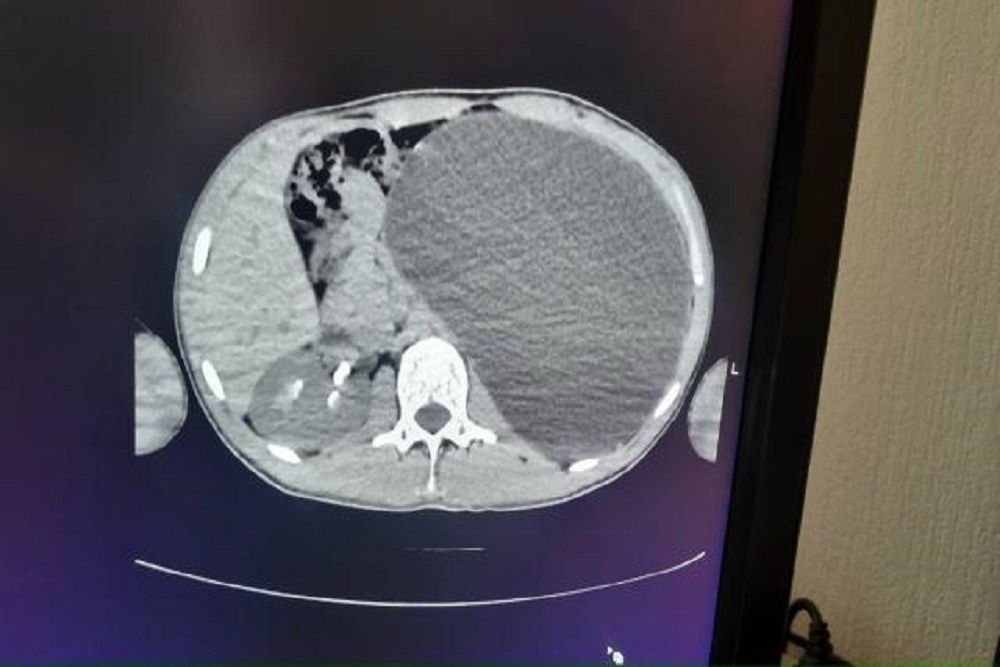

"У нашего пациента почка достигла размеров пятилитровой бутылки! Она занимала почти весь объем живота и давила на все соседние органы. Это была настоящая "бомба замедленного действия": любая травма, случайный удар в живот - и мешок мог разорваться внутри", - рассказали в Детской городской клинической больнице № 1.

"После того как в кабинете УЗИ было выдано заключение: "объемное образование, размер невозможно измерить, левой почки нет", пациент сразу был направлен в стационар детской городской клинической больницы № 1", - пояснили в минздраве Новосибирской области.

Через четыре небольших прокола хирурги откачали всю скопившуюся жидкость, а затем удалили поврежденный орган.